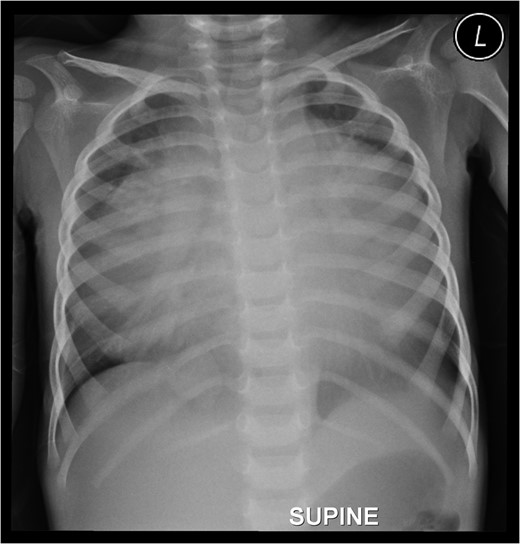

Preoperative chest roentgenogram showing cardiomegaly and massive pericardial effusion.